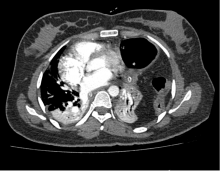

Figure 2. Contrast enhances the computed tomography scan of the chest. Transverse sections show abdominal contents in the left hemithorax with a collapsed ipsilateral lung. Moderate right-sided pleural effusion was also noted. Note is made of nasogastric tube in the stomach, seen in the left hemithorax. The stomach, descending colon, and omentum can be seen here in the left hemithorax compressing the ipsilateral lung.